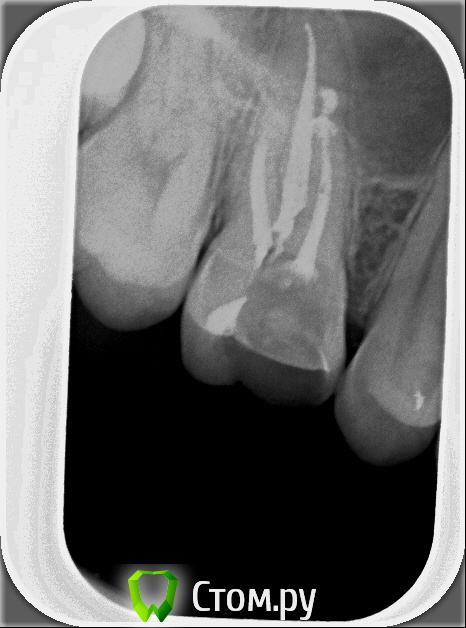

xSlon Опубликовано 13 августа, 2014 Поделиться Опубликовано 13 августа, 2014 Доброго времени суток!Прошу вашей помощи по сложному зубу, который не могут вылечить уже очень длительное время. Около 3х лет назад обнаружил, что при постукивании по 16му зубу(он был запломбирован совсем давно, не помню даже где и в каком году) появляется небольшая боль. Зуб не мешал, не доставлял беспокойств, но решив, что в таких случаях нужно действовать превентивно, пошел к стоматологу и рассказал о проблеме. Он посмотрел зуб(без вскрытия), сказал что никаких признаков боли не видит и считает что нужно удалять нерв. Поскольку зуб проблем не доставлял, я отказался.В течение этих трех лет состояние не ухудшалось, но я еще два раза ходил к разным стоматологам, описывал симптомы, они смотрели зуб, никаких признаков болезни не видели и советовали заниматься зубом когда он будет доставлять настоящие неудобства.В середине октября 2013 года ситуация ухудшилась, зуб начал периодически не сильно болеть, реагировать на холодное и горячее. В середине декабря ситуация сильно ухудшилась, зуб начал сильно болеть, сильно реагировать на холодное и горячее, сильно болеть даже при простом касании. Я обратился в стоматологию1 к врачу1, где мне вскрыли зуб, сказали что обнаружили под пломбой кариес, из-за кариеса произошло воспаление нервов и нужно удалять нервы в зубе. Боль была очень значительной, я не раздумывая согласился. Мне вскрыли зуб, поставили обезболивающее(или лекарство - точно не знаю), и сказали прийти через 7 дней, боль прошла. Через 7 дней мне обработали каналы и запломбировали Metapex'ом, сказали прийти в феврале(возможно еще удалили лекарство, точно не помню). В феврале мне за 1 посещение запломбировали постоянно каналы и за 2е посещение запломбировали зуб. К середине февраля лечение закончилось, жалоб не было. Единственное - удивляло что зуб, несмотря на удаление нервов, по старому реагирует на постукивание небольшой болью, но я не придал этому большого значения.Спустя 2 месяца, в середине апреля, остро заболел тот же самый зуб, с теми же симптомами - сильная боль, сильная реакция на холодное и горячее, сильная боль при касании. Врач1 был в отпуске, поэтому я пошел к Врачу2 в ту же самую Стоматологию1. Описал ситуацию, Врач2 посмотрела мою карточку, вскрыла зуб, осмотрела его, сказала что где-то должен быть 4й канал, но она не может его найти, сказала что вставила куда-то в зуб лекарство, сказала прийти через неделю.Боль утихла, пришел через неделю к тому же Врачу2, повторно вскрыли зуб, повторно поставили лекарство, но Врач2 сказала что 4го канала, который там должен быть, она не видит. Посоветовала обратиться к другому врачу, возможно, в другую стоматологию Через неделю, уже в начале мая, пришел повторно, запломбировали каналы Metapex'ом, поставили временную пломбу. По совету знакомых, в начале июня обратился к частному Врачу3, который специализируется на работе под микроскопом. Описал ей ситуацию, она вскрыла зуб, нашла четвертый канал, вставила туда лекарство, сказала прийти через неделю. Через неделю реакция зуба на слабые постукивания сохранилась, на приеме у Врача3 поставили более сильное лекарство(насколько я помню, с антибиотиком), прописала дополнительно в течении 5 дней пропить сильные антибиотики, сказала прийти через 10 дней. Через 10 дней, в конце июня, та же реакция зуба сохранилась. На приеме у Врача3 решили окончить лечение, потому как Врач3 на следующий день уходила в отпуск, а я, через несколько дней, уезжал в командировку. Перед отъездом пошел в Стоматологию1 к Врачу2, чтобы снять лекарство и временно запломбировать каналы и поставить временную пломбу. Врач2 сказала, что при вскрытии зуба она увидела 4й канал, попыталась определить длину канала с помощью прибора, используя самый тонкий инструмент(как я понял - это некая игла, подсоединенная к прибору, ее всовывают в канал, чем ближе кончик иглы к концу канала, тем сильнее он пищит), определить длину канала ей не удалось. Она предположила, что либо канал очень узкий, либо он изгибается, поэтому не удается дойти до конца канала.В командировке, в середине июля обновлял временную пломбу(от нее отвалился небольшой кусочек) в Стоматологии2, вкратце описал проблему Врачу4, он посоветовал использовать(дословно с листочка, который он мне дал) пломбировку материалом для к/к Forfenan Forident(резорцин-формалиновая паста). Сказал, что при таком методе, воспаленный нерв полностью обволакивается пастой, которая гермитизирует нерв, не давая разиваться воспалительному процессу. Сам воспаленный нерв остается, но организм, со временем, справляется с ним сам.Вернувшись из командировки, я пошел, по советам родственников, в Стоматологию3, к Врачу5. Описал ситуацию, сделал панорамный и прицельный снимки. Врач5, не вскрывая зуб, сказала что считает, что необходимо применить метод депофореза. Прошу вас, пожалуйста, посоветовать, каким образом вылечить этот зуб? Стоит ли попробовать резорцин-формалиновую пасту? Стоит ли делать метод депофореза? Возможно есть какие-то другие методы лечения? Прикладываю все снимки зуба из Стоматологии1Панорамный снимок из Стоматологии3, сделан 12 августа. https://yadi.sk/i/_hIqGP1IZaT4Y Ссылка на комментарий

Scrabble Опубликовано 31 августа, 2014 Поделиться Опубликовано 31 августа, 2014 Я вижу, что Вам запломбировали каналы термафилами-причём два носителя введены в дистальный, а не в мезиальный щёчный корень. В качестве силера(пасты) использовался форфенан? Если это так, то нужно всё распломбировать, полностью удалить форфенан-и ждать, пока стихнет симптоматика. Ссылка на комментарий

xSlon Опубликовано 8 сентября, 2014 Автор Поделиться Опубликовано 8 сентября, 2014 Позвонил Врачу3, проконсультировался с ней - она посчитала что ее вмешательство не нужно, имеет смысл сходить к Врачу2, просто поставить временную пломбу.Ходил 03.09.14 к Врачу2 в Стоматологию1 - сменили метапасту в небном, дистально- и медиально-щечном, медианно-небном поставили жидкость форадент, поставили временную пломбу СИЦ.Я вижу, что Вам запломбировали каналы термафилами-причём два носителя введены в дистальный, а не в мезиальный щёчный корень. В качестве силера(пасты) использовался форфенан? Если это так, то нужно всё распломбировать, полностью удалить форфенан-и ждать, пока стихнет симптоматика.Просмотрел всю карточку из Стоматологии1, слова форафен там не нашел. Скажите, пожалуйста, на каком снимке вы это увидели? Ссылка на комментарий